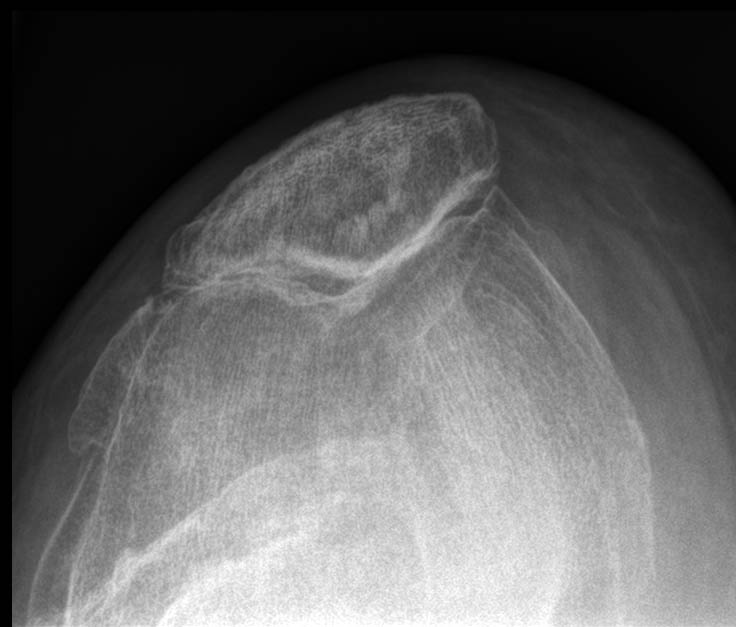

Fractura impactada de húmero .

Fractura de húmero, intensa desviación de fragmentos

Fractura de húmero.

Fractura compleja de húmero.